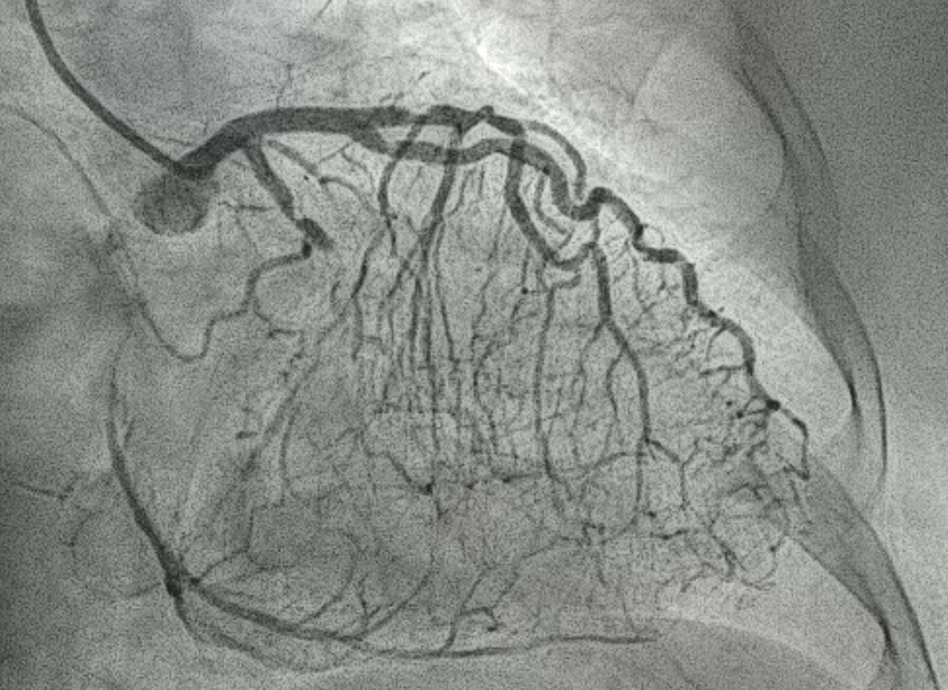

The SAL1 guiding catheter was unstable, jumping in and out the ostium. We deployed PK Papyrus 2.5 x 20 mm stent graft to dRCA quickly and planned to deployed another DES to p-dRCA. However, the patient agitated and the whole system was removed, leaving severe spiral dissection, starting from the ostium to middle RCA.We tried to wire FC, XTA and sion balck to true lumen but fail. Switched to 6F JR guiding but still fail.We wired FC to distal RCA with parallel wire technique and checked IVUS. The distal wire was over true lumen, but false lumen wiring was noted since proximal RCA.We wired XTA to true lumen under IVUS image. Then true lumen wiring was completed.We dilated with 1.5 balloon. Followed by Ryurei 2.50 x 15 mm to mRCA.We deployed Ultimaster Tansei 3.00 x 38 mm and Ultimaster Tansei 4.00 x 18 mm to p-dRCA.Post-dilated with 3.0, 3.5, and 4.0 NC balloon to RCA.The final IVUS showed well stent expansion.The final flow is good. We closed the procedure smoothly.